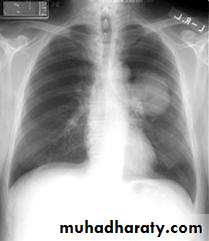

Common radiological presentations of bronchial carcinoma

*Unilateral hilar enlargement*Peripheral pulmonary opacity

*Lung, lobe or segmental collapse *Pleural effusion

*Broadening of mediastinum, enlarged cardiac *shadow, elevation of a hemidiaphragm

*Rib destruction